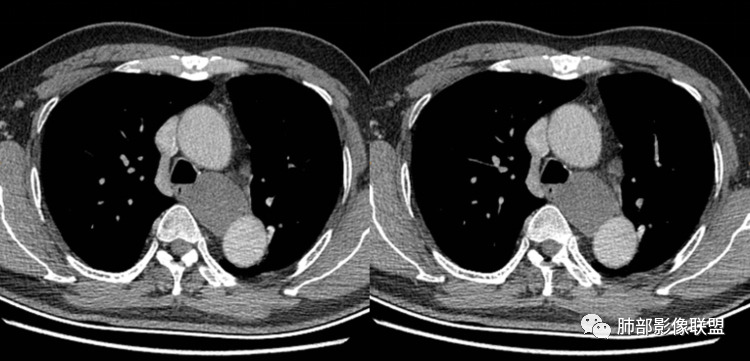

男性,43岁,体检发现后纵隔占位,边缘光整,CT示密度均匀,周围组织受压移位,无钙化囊变及脂肪组织,增强未见明显强化。MRI:T1示肿块信号较肌肉高,T2不均匀高信号。考虑为良性病变,第一是神经节细胞瘤,其次是支气管源性囊肿。

后纵隔囊性占位,密度均匀,与左主支气管分界不清,略受压,增强后强化不明显,核磁上看肿块局部突出,信号欠均匀,考虑良性,节细胞神经瘤可能大,支气管囊肿待排。

左后纵隔食管旁占位,边界清晰,增强目测未见明显强化,稍长T1稍长T2信号,信号尚均匀,病灶较软,和食管紧贴,定性良性,首先考虑前肠囊肿,以支气管囊肿可能性大,鉴别节细胞瘤。

(3)若囊肿内密度较高时与实性肿块鉴别较为困难,增强扫描囊液无强化为鉴别要点;但是囊壁因为含有平滑肌成份,所以可能环形强化;如果病灶合并感染,病灶壁也会明显强化。

(5)张力不高时可以形态柔顺,成份复杂时可以密度较高,但内部不会强化。